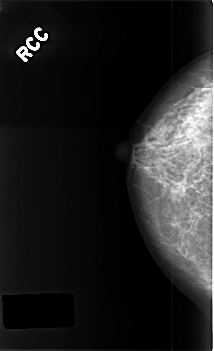

ics_version 1.0 filename C-0385-1 DATE_OF_STUDY 20 5 1996 PATIENT_AGE 40 FILM FILM_TYPE REGULAR DENSITY 2 DATE_DIGITIZED 9 11 1998 DIGITIZER LUMISYS LASER SEQUENCE LEFT_CC LINES 4464 PIXELS_PER_LINE 2872 BITS_PER_PIXEL 12 RESOLUTION 50 OVERLAY LEFT_MLO LINES 4432 PIXELS_PER_LINE 2856 BITS_PER_PIXEL 12 RESOLUTION 50 OVERLAY RIGHT_CC LINES 4560 PIXELS_PER_LINE 2776 BITS_PER_PIXEL 12 RESOLUTION 50 NON_OVERLAY RIGHT_MLO LINES 4576 PIXELS_PER_LINE 2808 BITS_PER_PIXEL 12 RESOLUTION 50 NON_OVERLAY |